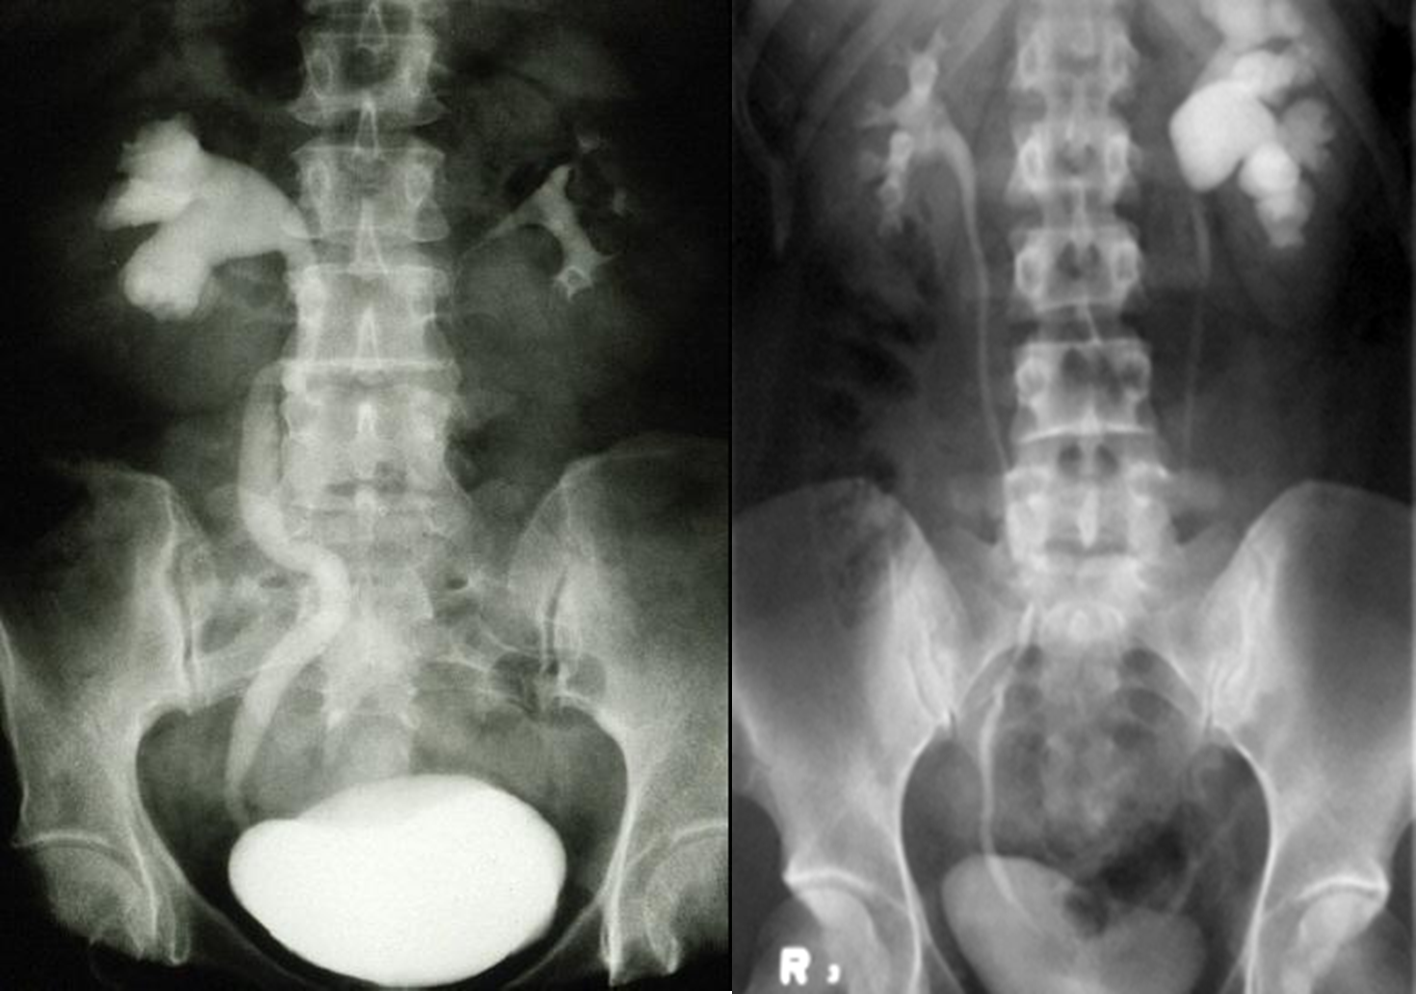

Distension and dilation of the renal pelvis and calyces.

It is usually caused by obstruction to the free flow of urine from the kidney.

If obstruction is at lower level, there is dilation of ureter and pelvis of kidney.

Untreated , initially it cause enlargement of kidney, but finally it leads to atrophy.